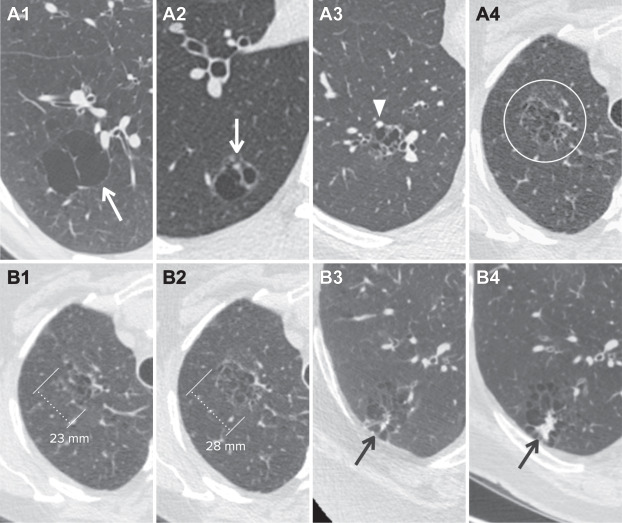

- Nang nhiều ngăn có các vách ngăn bên trong và có thể có liên quan thành phần kính mờ hoặc thành phần đặc (Hình 3).

- Nang thành dày và nang nhiều ngăn được phân loại là Lung-RADS 4A với khuyến cáo quản lý bằng CT liều thấp (LDCT) sau 3 tháng hoặc PET/CT nếu có thành phần đặc ít nhất 8 mm.

- Gia tăng độ dày thành hoặc nốt của nang thành dày, tăng số lượng ngăn của nang có nhiều ngăn, gia tăng hoặc xuất hiện thành phần mờ mới (nốt, kính mờ hoặc đông đặc) bên trong hoặc sát bên nang nhiều ngăn được phân loại là 4B với khuyến cáo đánh giá chẩn đoán phù hợp (Hình 3).

Hình 3. Nang phổi không điển hình: nhiều ngăn. (A) Nang phổi nhiều ngăn có hình dạng không đồng nhất, chứa các vách ngăn bên trong (A1, A2, A3, A4) và có thể có các thành phần đặc hoặc dạng kính mờ như thành dày (A2, mũi tên), nốt (A3, đầu mũi tên), hoặc các vùng mờ bên trong (hình tròn). Nang phổi nhiều ngăn được phân loại là Lung-RADS 4A tại thời điểm ban đầu. (B) Một bệnh nhân 68 tuổi có nang phổi nhiều ngăn có đường kính trung bình là 23 mm tại thời điểm ban đầu (B1), phát triển thành 28 mm khi sàng lọc CT 12 tháng (B2). Một bệnh nhân 56 tuổi có nang phổi nhiều ngăn chứa thành phần đặc tại thời điểm ban đầu (B3, mũi tên) phát triển khi sàng lọc theo dõi (B4, mũi tên). Các nang nhiều ngăn phát triển (đường kính trung bình tăng >1.5 mm), có nhiều ngăn hơn, hoặc có thành phần mờ mới hay gia tăng thì rất nghi ngờ ác tính và được phân loại là Lung-RADS 4B.